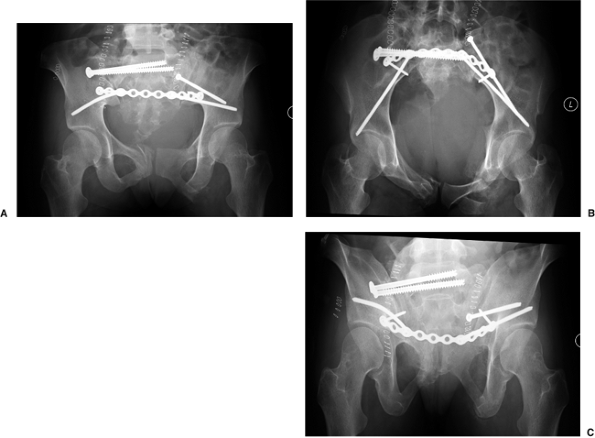

postoperative radiographs taken after open reduction and iliosacral

screw fixation of the right sacral fracture and lag screw fixation of

the left PSIS fracture. Because of the bilateral posterior pelvic-ring

injuries, dorsal tension-band plating

of

the sacrum was chosen to augment the screw fixation. The patient’s

abdomen was left open for an extended period because she experienced an

abdominal compartment syndrome. The anterior pelvic-ring injuries were

not operatively addressed and were allowed to heal without fixation.

Figure 40.18.

Postoperative radiographs after posterior pelvic-ring fixation. The fracture of the mammillary process of the right sacral ala may be mistaken for persistent gross cranial translation of the fracture. However, the heights of the iliac wings and the restoration of the sacral foramina seen on the cephalad view demonstrate that much of the displacement has been corrected. Persistent incongruity is seen in the left sacroiliac joint because of the comminution and impaction of the sacral side of the joint. The symphyseal fragment remains rotated. |